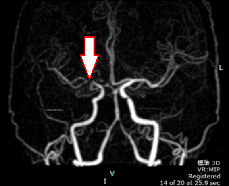

頭蓋内動脈狭窄症

左側の中大動脈が狭窄しており、血流が滞っています。

この状態を放置すると脳梗塞を発症するリスクがあります。

頭蓋内動脈狭窄症(MRA)